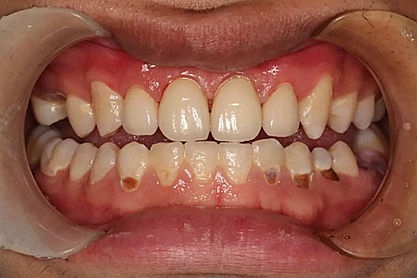

現(xiàn)在剩下的任務(wù)就是為我其他的兄弟姐妹們治療了。需要做根管的做根管,需要做冠的做冠,需要樹脂充填的做樹脂充填。前前后后主人帶我們進行了12次的復(fù)診,歷時6個月,現(xiàn)在的我們是這樣的

再來看看曾經(jīng)的我們